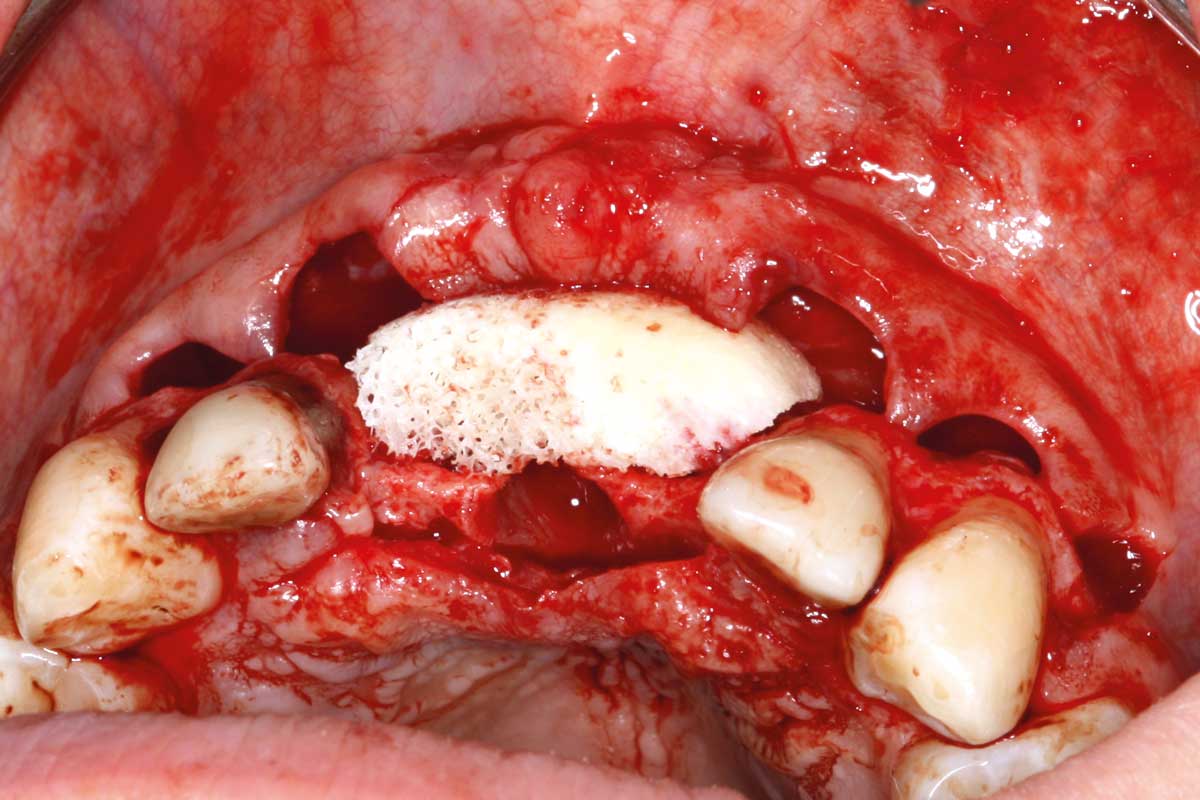

05/26 - Positioning of maxgraft® bonebuilder

Ridge augmentation in the maxilla with maxgraft® bonebuilder in the aesthetic zone - Dr. M. Kristensen